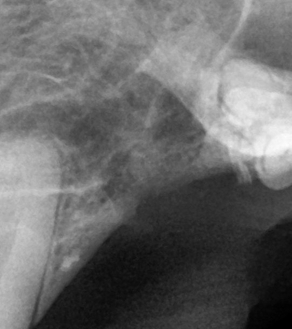

BEFORE

AFTER